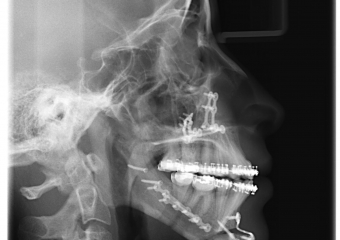

Telerradiografia inicial

Telerradiografia após a cirurgia